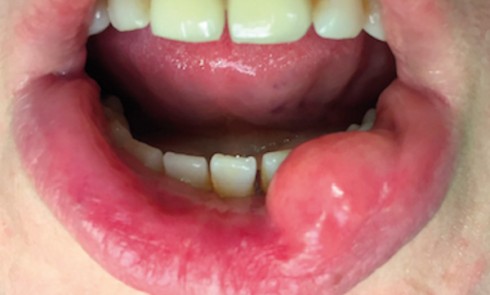

Article réservé à nos abonnés À propos d’une lésion labiale

1. Quel diagnostic évoquez-vous ?a. Un lymphomeb. Un kyste salivairec. Un carcinome épidermoïded. Aucun de ces diagnostics 2. Quelle attitude préconisez-vous ?a....